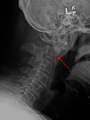

A fracture of the base of the dens as seen on plain X ray